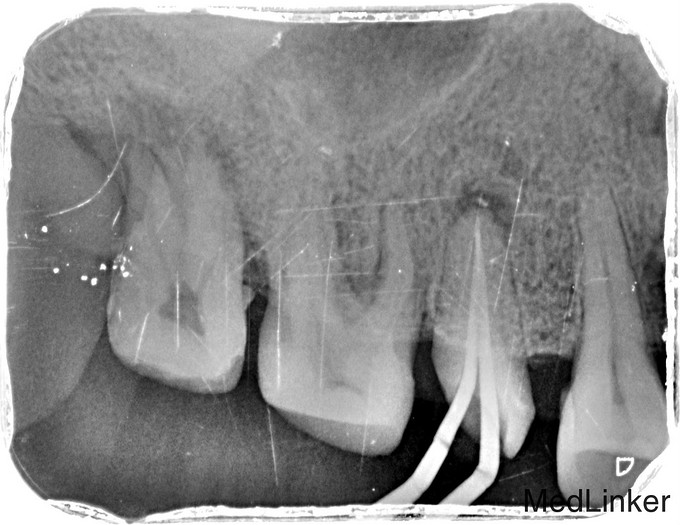

临床检查:15牙合面充填物部分脱落,探痛(+),冷(++),叩(+),松动度(-),牙周正常. 可探及穿髓点,有窦道。 辅助检查:X线示15龋坏累积髓腔,根尖周牙周膜增宽。根尖部阴影。

诊断:15根尖周炎 治疗:经患者知情同意后,15局麻去腐降牙合,开髓拔髓寻找根管口,建立直线通路,扩通根管,确定工作长度。S3/EDTA凝胶镍钛器械,低浓度次氯酸钠冲洗根管,预备至35/04,氢氧化钙诊间封药,一周后复诊,试主尖X线示恰充,试干根管,导AH-PLUS糊剂,VDW热压胶垂直加压根充,术后见根管恰充,暂封调合抛光观察。考虑桩冠修复。